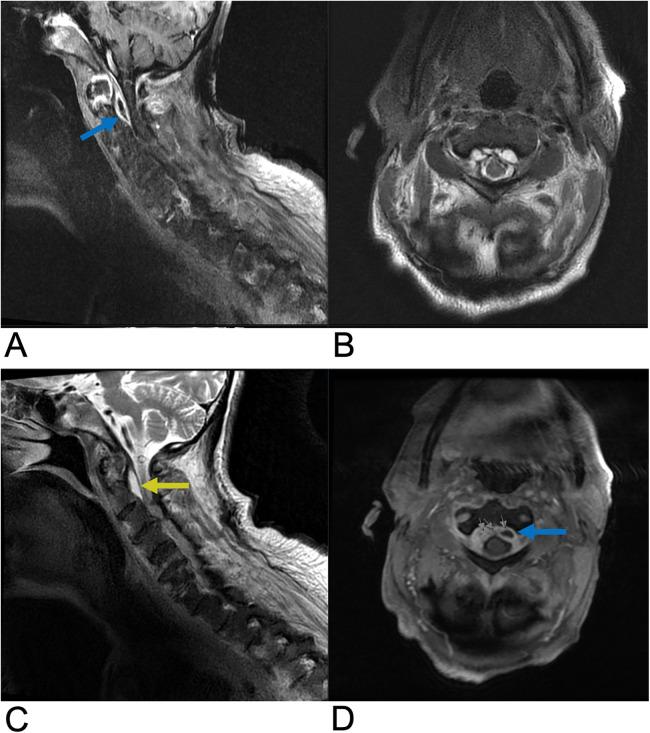

Spinal lesions encompass a diverse range of pathologies, including primary and secondary tumors, infectious processes, vascular malformations, traumatic injuries, and degenerative conditions, each with distinct imaging characteristics crucial for accurate diagnosis and management. Imaging plays vital roles in assessing lesion morphology, anatomical localization, and neurological impact, guiding clinical decision-making and therapeutic planning. This review systematically explores spinal lesions based on their anatomical compartments, highlighting key radiological features and providing a comprehensive reference for radiologists.